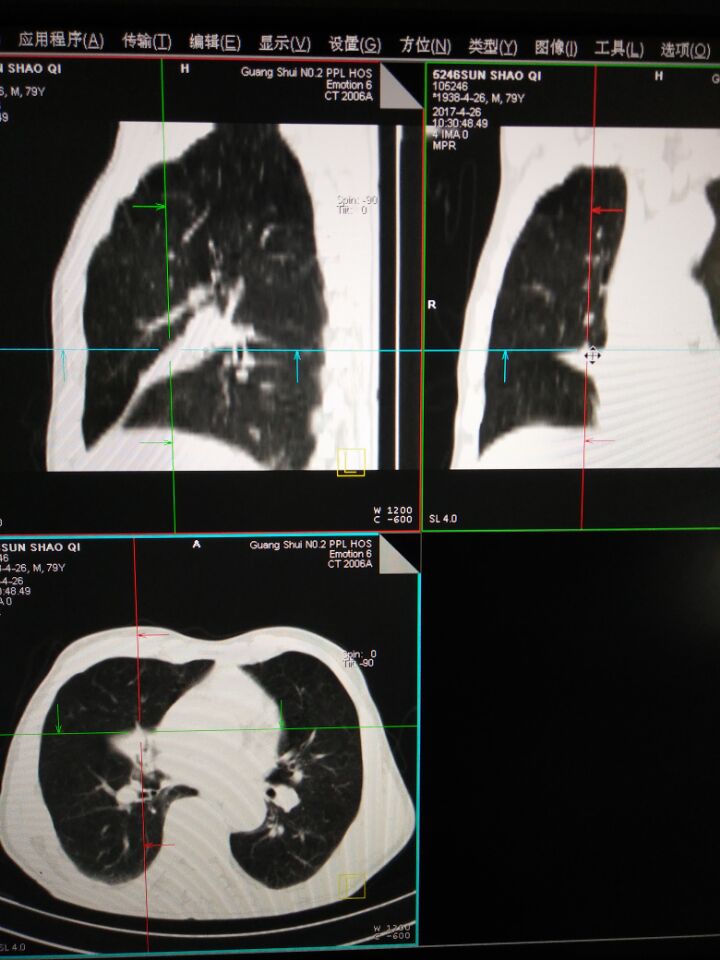

CT52765:男76岁,咳嗽二十年,近几天加重

男76岁,咳嗽二十年,近几天加重

中叶不张 官腔好像有软组织密度结节

右肺中叶可见尖端指向胸壁三角形不张影。考虑:右肺中叶不张,建议支气管镜检查。

右中叶肺不张。原因待定。

建议:气管镜检查。

(右中叶肺不张常见原因:肿瘤、肺炎、支气管结石、支气管内膜结核、老年性中叶综合征等)

右肺中叶不张,建议支气管镜检查。